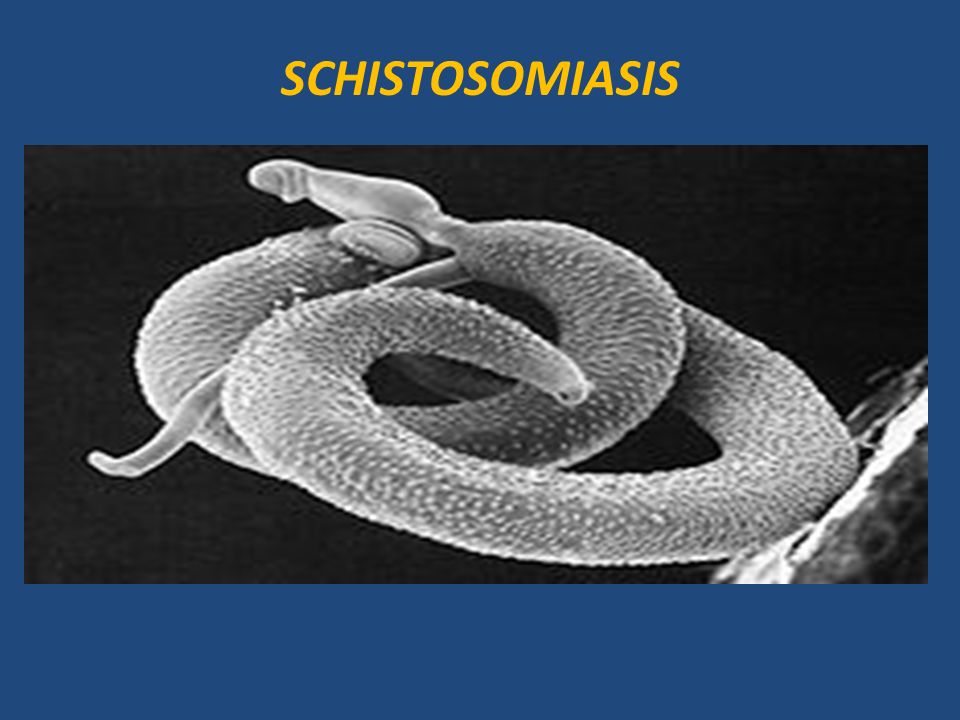

Шистосомоз: что нужно знать о паразитах